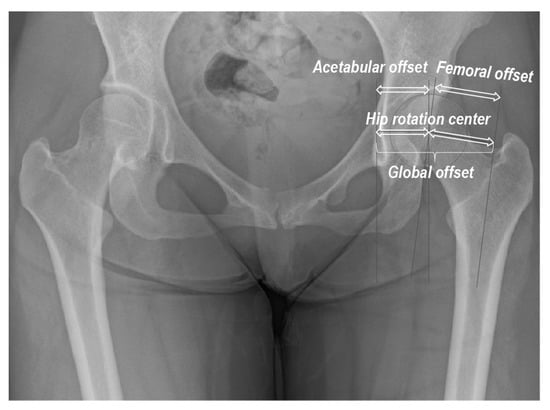

| Global offset (mm) | 80.9 (8.8) | 72.6 (5.9) | <0.001 |

| Acetabular offset (mm) | 37.7 (4.0) | 34.2 (2.4) | <0.001 |

| Femoral offset (mm) | 43.2 (8.3) | 38.4 (5.0) | 0.005 |